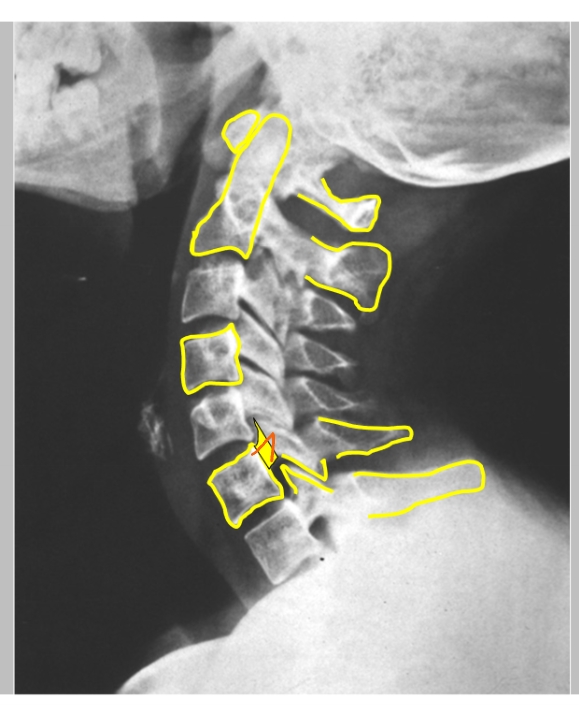

schuine opname = oblique view

foramen intervertebrale C4-C5 (links)

daaruit komt spinale zenuw C5

processus uncinatus (linker)

pedikel (linker)

spinale zenuw → gaat richting duim

= uncartrose C5-C6 (links)

klachten: cervico-brachialgie

blauwe gedeelte = osteofiet → vernauwing van foramen intervertebrale door verbening

zenuw heeft bijna geen plaats meer en wordt gekneld → last vanuit nek straalt uit naar duim

dermatoom

= uncartrose C6-C7 (links)

klachten: cervico-brachialgie

blauw gedeelte = osteofiet

pijn straalt uit naar 2e, 3e en radiale helft 4e vinger